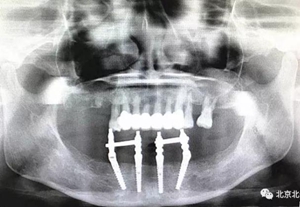

沒有假貨,貨真價(jià)實(shí),完成三年復(fù)查。

圖二十三:有圖有真相。

圖二十四:2017年11月復(fù)查時(shí)照片,植體很穩(wěn)定, 無骨吸收。